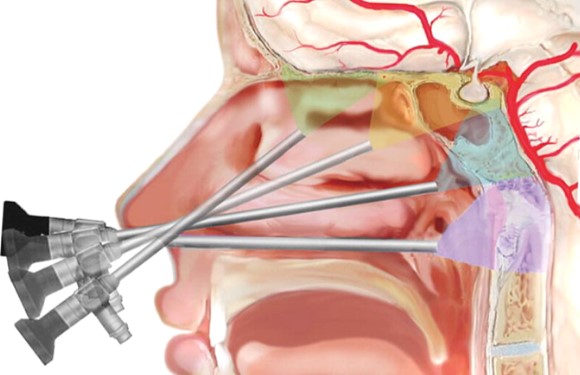

Pituitary gland is situated in the centre of the head below the brain, behind the eyes and above the back of the nose. It controls other endocrine glands – Thyroid, adrenal glands, ovaries, breast in women and testes in men. It also secretes growth hormone and anti-diuretic hormone.

A tumor from this gland may secrete hormones excessively (even when <10mm, called Microadenoma) causing conditions like Acromegaly, Cushing’s disease, or infertility-related syndromes. Non-functioning tumors can grow and compress nearby structures, leading to vision problems or hormone deficiency. Many are detected incidentally during scans.